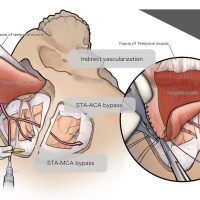

術後イラストシリーズ